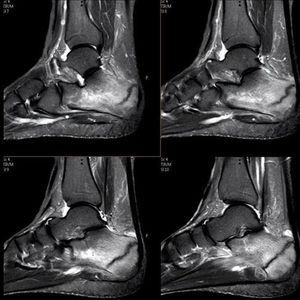

Musculoskeletal MRI. Calcaneus fracture.

Mri

Msk